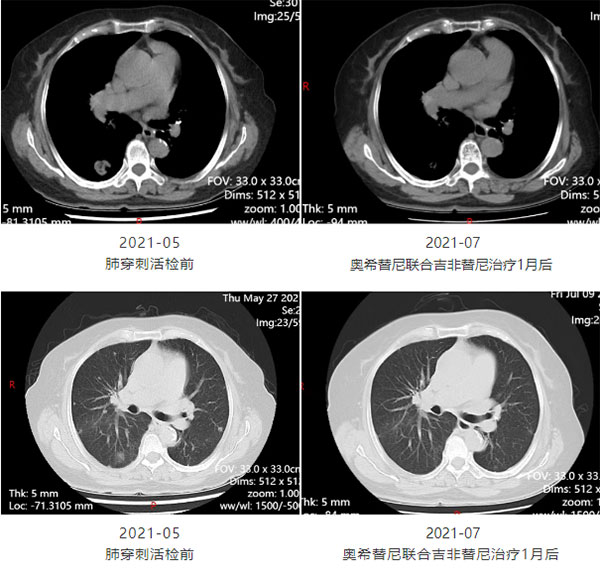

2021 年的穿刺活检报告如同复杂密码:EGFR 19 缺失突变叠加 T790M 与 C797S 反式突变。在多学科会诊室的白板上,肿瘤科、影像科、放疗科医生用不同颜色的笔勾勒治疗路径:奥希替尼联合吉非替尼的 “双靶策略” 让右肺肿瘤缩小 30%,肝脏转移灶的介入治疗与脑转移放疗接力上阵。那段时间,她的床头柜摆满了治疗日志,用红笔在“CEA 值”旁画笑脸,“医生说这像打游击战,咱们得比癌细胞更会迂回。”

有图有真相

治疗效果